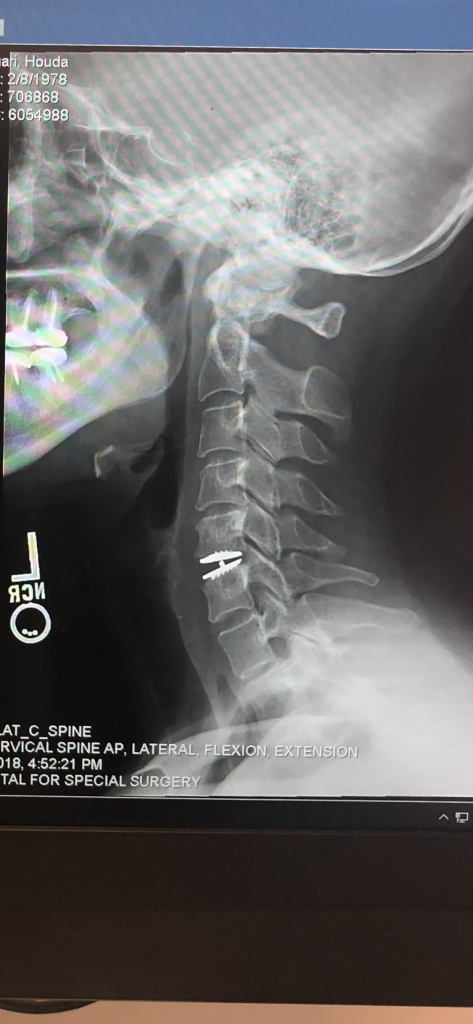

Dr. Huang gave me my life back! I was diagnosed with a C5-C6 disk herniation 2 years ago which would cause extreme pain from my neck down to my whole left side shoulder and arm. I tried everything to treat it from physical therapy to acupuncture to epidurals and medication (nerve pain and muscle relaxers). The pain was debilitating. I was finally told by Dr. Robert Griffin at HSS that I should consider surgery. He recommended 3 surgeons to me and Dr. Huang was one of them. After doing my research I chose to go with Dr. Huang. The staff at the HSS Integrative Center (where I was getting my PT) all spoke very highly of Dr. Huang and told me if went with him, I was in good hands. What I appreciated about Dr. Huang is that he first reviews your medical file, MRIs and x-rays before meeting with you to decide if you are a good candidate for surgery. From the initial consultation appointment I felt so at ease and comfortable with him. He went over all my MRI images with me and patiently explained what the images revealed and which surgery options were available in my case. I asked Dr. Huang many questions, which he answered thoughtfully. I never felt rushed. He thoroughly explained the procedure, expectations and risks as well. He was very cordial and calming at the end of the visit. It took me a couple of days to decide I was going to proceed with the surgery with Dr. Huang and I’m so happy I did! I had my surgery 11 weeks ago and I feel great! Dr. Huang performed a total disc replacement at C5–C6. Recovery was not so bad at all. His staff is excellent. HSS is a great hospital. I can finally live pain free! Thank you so much Dr. Huang!!!